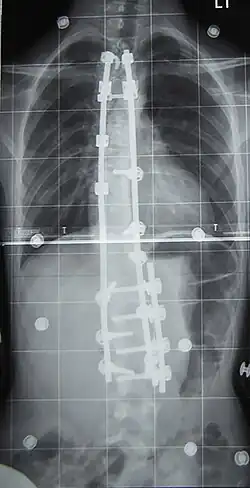

Surgery

Surgery is usually recommended by orthopedists for curves with a high likelihood of progression (i.e., greater than 45–50° of magnitude), curves that would be cosmetically unacceptable as an adult, curves in people with spina bifida and cerebral palsy that interfere with sitting and care, and curves that affect physiological functions such as breathing.[104][105]

Surgery is indicated by the Society on Scoliosis Orthopaedic and Rehabilitation Treatment (SOSORT) at 45–50°[4] and by the Scoliosis Research Society (SRS) at a Cobb angle of 45°.[106] SOSORT uses the 45–50° threshold as a result of the well-documented, plus or minus 5° measurement error that can occur while measuring Cobb angles.[106]

Surgeons who specialize in spine surgery perform surgery for scoliosis. To completely straighten a scoliotic spine is usually impossible, but for the most part, significant corrections are achieved.[107]

The two main types of surgery are:[108]

- Anterior fusion: This surgical approach is through an incision at the side of the chest wall.

- Posterior fusion: This surgical approach is through an incision on the back and uses metal instrumentation to correct the curve.

One or both of these surgical procedures may be needed. The surgery may be done in one or two stages and, on average, takes four to eight hours.

In the 1980s, Cotrel–Dubousset instrumentation improved fixation and addressed sagittal imbalance and rotational defects unresolved by the Harrington rod system. This technique uses multiple hooks with rods to give stronger fixation in three dimensions, usually eliminating the need for postoperative bracing.[120]